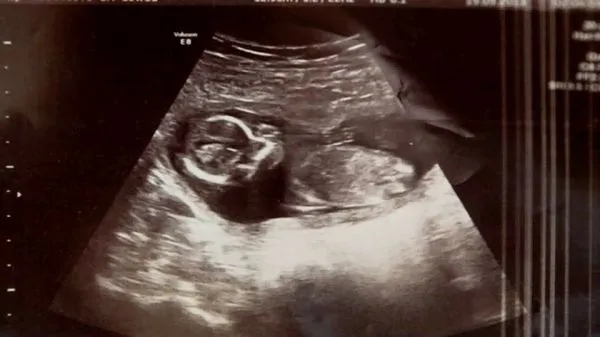

Перед проведением неприятной процедуры врачи решили еще раз сделать УЗИ, во время которого обнаружили сердцебиение еще одного младенца! Мишель была по-прежнему беременна. Так получилось, что изначально женщина вынашивала близнецов, одного из которых потеряла в самом начале срока. Опытные врачи госпиталя Ротунды в Дублине не могли объяснить, как второй малышке удалось выжить, несмотря ни на что!

«Доктор вышел, а потом вернулся со своим коллегой. Тот вновь провел УЗИ и сказал: «Вы не поверите, но мы слышим сердцебиение!» — рассказывает Мишель. — Это была самая счастливая минута в моей жизни!» Малышка Меган появилась на свет красивой и здоровой, чем не на шутку удивила врачей и своих родителей.